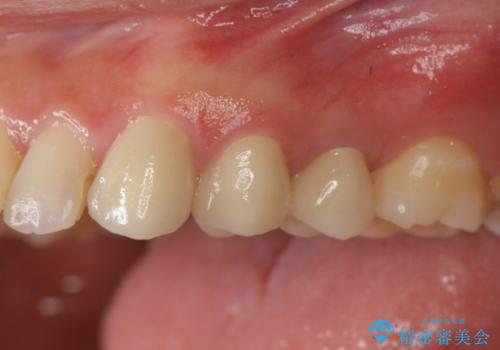

- [ 再生治療・歯周外科・小矯正・セラミック補綴 ] 前歯の歯周病治療- 担当医 大元洋佑 ![[ 再生治療・歯周外科・小矯正・セラミック補綴 ]  前歯の歯周病治療の症例 治療前](https://seimitsushinbi.jp/wp/wp-content/uploads/2022/12/83065c2454a29ed71cf190e15a6106f4-500x350.jpg?v=1671673398) ![[ 再生治療・歯周外科・小矯正・セラミック補綴 ]  前歯の歯周病治療の症例 治療後](https://seimitsushinbi.jp/wp/wp-content/uploads/2022/12/ec16e37ee53325a6f6629b94759f5513-500x350.jpg?v=1671673454)